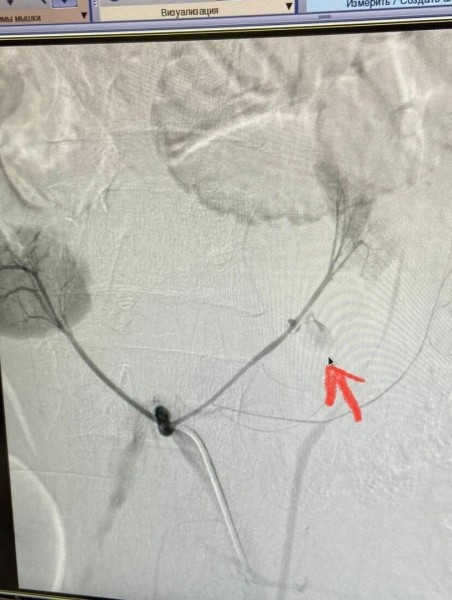

Его удалось найти после мультиспиральной компьютерной томографии. У пациента оказалась дополнительная почечная артерия, которая образовывала единый орган.

«Вместо двух почек, как у обычного человека, мы увидели одну большую подковообразную почку. А на КТ была обнаружена ещё и дополнительная артерия, которая выходит из подвздошный артерии и питает нижние полюса почки. Именно она повредилась при падении и дала кровотечение. И сложность состояла в том, что во время операции предстояло бороться за сохранность уже не одной почки, а сразу двух», — вспоминает подробности врач-рентгенхирург.